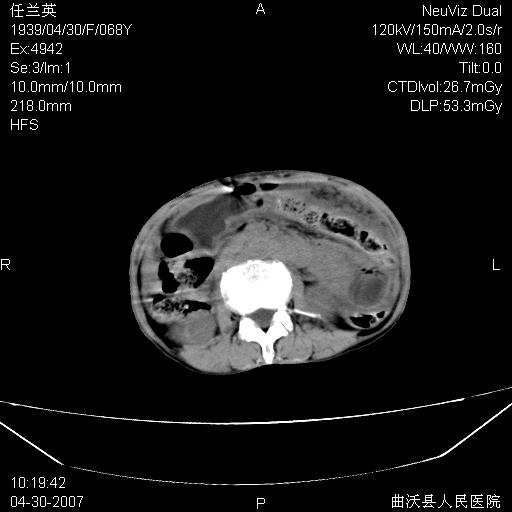

患者,女,68岁,感觉腹部憋涨发硬数天,查b超发现左盆腔有囊性肿物和少量腹水,行ct检查

1.考虑卵巢肿瘤并腹腔广泛性转移可能性大;

2.腹盆腔少量积液。

支持左侧卵巢恶性肿瘤伴网膜、腹膜广泛转移。

难的一见 典型 - 网膜饼  冰冻骨盆 可以当教学片了